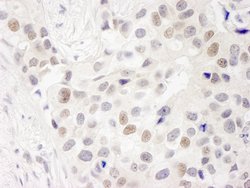

INT7 Polyclonal Antibody, Bethyl Laboratories

Rabbit Polyclonal Antibody

Supplier: Bethyl Laboratories, Inc IHC00413T

Integrator complex subunit 7 (INT7) is a component of the Integrator complex. The Integrator complex is a complex associates with the C-terminal domain of RNA polymerase II and mediates 3′-end processing of the small nuclear RNAs U1 and U2. It plays a role in DNA damage response signaling during the S phase.Specifications

| Immunohistochemistry | |